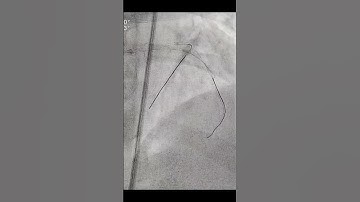

Instant variable stiffness in cardiovascular catheters based on fiber jamming